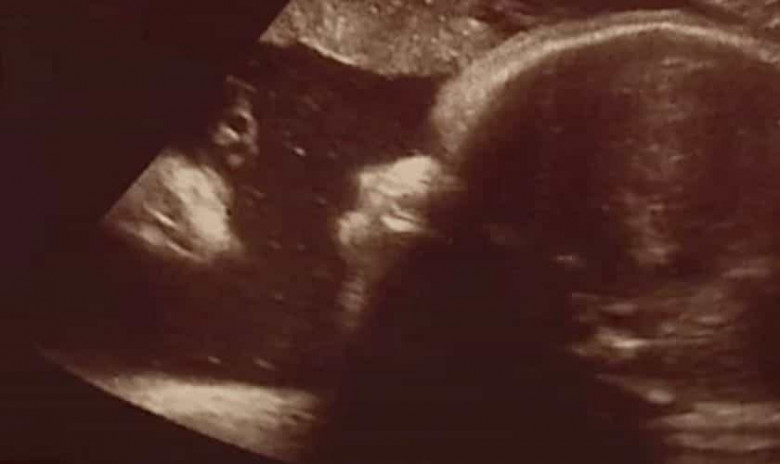

Զույգը պնդում է, որ Քրիստոսն իրենց դեռ չծնված պտղի կողքին էր՝ կնոջ արգանդում

ՖՈՏՈՇատ քրիստոնյաներ հաճախ ասում են, որ Քրիստոսն ամենուր է։ ԱՄՆ Փենսիլվանիայում բնակվող մի զույգի համար «ամենուր»-ը ներառում էր նաև կնոջ արգանդում գտնվող պտղի սոնոգրամային հետազոտությունը։

Չեմբերսբուրգի շրջանում ապրող Ալիսիա Ցիքն ու Զեք Սմիթը Fox 43-ին են փոխանցել Հարիսբուրգի հիվանդանոցու արված սոնոգրամային հետազոտության նկարը, որում կարծես՝ մի մարդ կողքից նայում է իրենց պտղին։

«Երբ այն տվեցին մեզ, միանգամից նկատեցի, որ նա Հիսուսն է»,-ասել է կինը։ Իսկ ամուսինն էլ պատմել է, որ նկարին նայելուց հետո սկսել է արտասվել․ «Չէի կարողանում խոսել, հավատս չէր գալիս։ Աչքերիս չէի հավատում»։